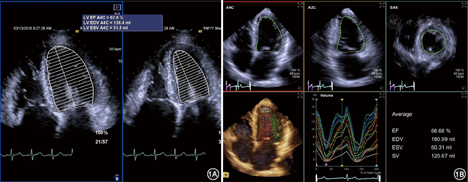

应由二维(双平面Sipmson法)(图1A)或三维超声方法测定左心室舒张末期(EDV)和收缩末期(ESV)容积[当左心室形态正常且无节段性室壁运动异常时,也可由M型超声Teichholz法获得,但最新美国超声心动图学会(ASE)/欧洲心血管影像学会(EACVI)指南中已不再推荐使用[1]]。射血分数(EF)=(EDV-ESV)/EDV×100%。LVEF不仅广泛应用于临床决策,同时是大多数心脏疾病临床预后的预测因子。另外,LVEF与年龄、性别和体表面积无明显相关性。成人LVEF正常参考值范围:53%~73%。

注:A4C心尖四腔心切面;EDV舒张末期容积;ESV收缩末期容积;SV每搏量

二维双平面Simpson法是临床上测量EF最常用的方法,但是有条件的单位应尽量采用三维超声心动图(图1B)连续评估左心功能不全患者LVEF,因为三维超声心动图的时间变异性通常在6%以下,远低于其他技术(10%左右)。同时,三维超声心动图还具有最小的观察者内部、观察者之间的变异性。